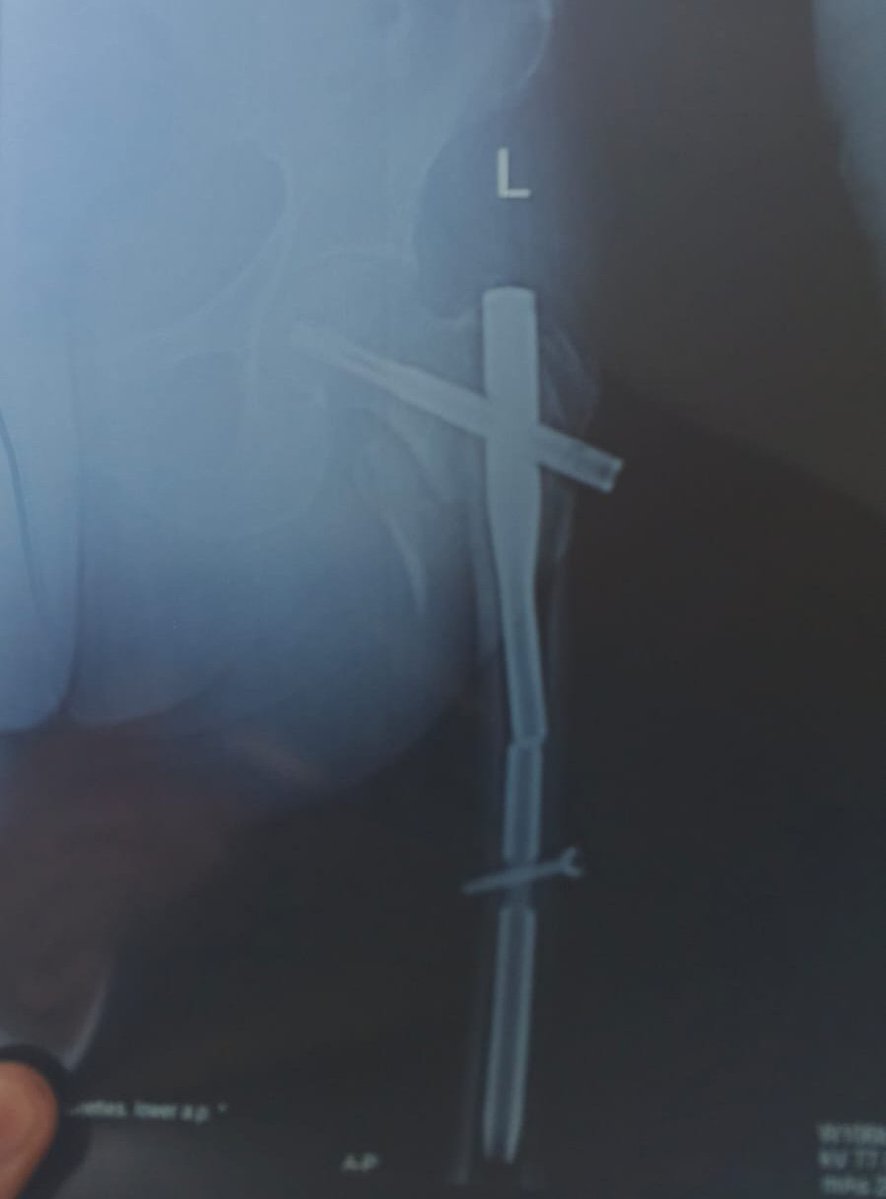

I’m bionic for real now 🦾